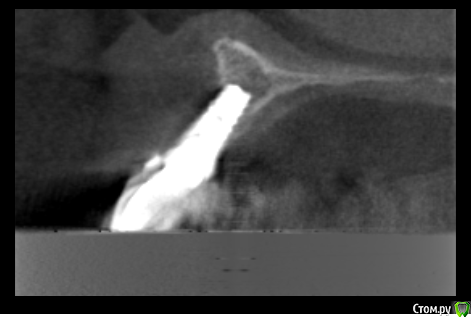

ikaZonter Опубликовано 27 апреля, 2016 Поделиться Опубликовано 27 апреля, 2016 Здравствуйте уважаемые коллеги! Год назад пациентке был установлен имплант в поз 21.на контрольном осмотре ч\з 9 мес , имплант подвижен. на кт вестиб. стенка ушла полностью.Посоветуйте как поступить в плане восстановления, блок или графт+ каркасная мембрана? во сколько этапов?Заранее всем спасибо! Ссылка на комментарий

Kovalov Igor Опубликовано 27 апреля, 2016 Поделиться Опубликовано 27 апреля, 2016 А на кт вестибулярки неивидно не от того что фонит металл ? Ссылка на комментарий

ikaZonter Опубликовано 28 апреля, 2016 Автор Поделиться Опубликовано 28 апреля, 2016 хочет сохранить имплант сохранить ? даже не думал об этом. Имплант убирать однозначно, вопрос в том как поступить дальше?! вестибулярки неивидно не от того что фонит металл ? к сожалению не фонит .((( Ссылка на комментарий